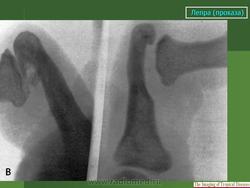

Что касается нервной формы проказы (рис. 216), то наиболее ранним, постоянным и общим рентгенологическим ее проявлением служит остеопороз. IK остеопорозу рано присоединяются явления остеолиза. Иконография (т. е. описание картины) остеолиза дается различными авторами в традиционном для лепрологии стиле в чрезвычайно тонких и кропотливых внешне описательных образах. Здесь преобладают сравнения с общеизвестными предметами, как, например, отточенными кончиками карандаша, шахматными пешками и другими фигурами, кнопками, пуговицами для воротника, запонками, тающими свечами, обсосанными леденцами, столбиками, иглами и т. д. Существенно то, что налицо частичное или полное рассасывание и исчезновение костных элементов без их замещения другой тканью и без продуктивной репаративной реакции. Характерно истончение и укорочение костей, в первую очередь ногтевых фаланг. Рассасывание ногтевой фаланги начинается с ее ногтевого отростка. Структура бугорка становится крупнопористой, ноздреватой. Затем срезается дистальный или боковой край, развивается плоская или вогнутая узура, постепенно увеличивающаяся, а затем и весь ногтевой отросток сходит на нет; обнажается шейка. Основание фаланги рассасывается с одного края или с обеих сторон, иногда и целиком. В дальнейшем без каких-нибудь клинических признаков очередь доходит до фаланг средних и основных, а также пястных и плюсневых костей, с переходом на запястье и предплюсну, порой до полного исчезновения скелета одного, нескольких, многих или всех пальцев.